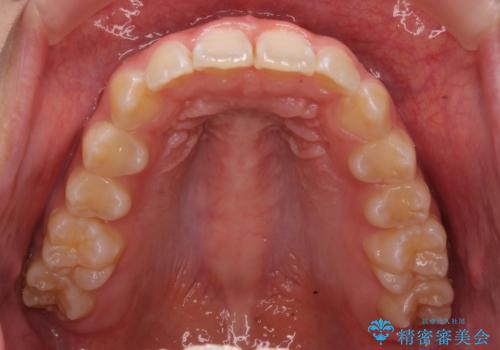

前歯の並び インビザライン 非抜歯で 深いかみ合わせの治療

- 前歯の並びを気にして来院。

上の前歯が内側に倒れこんでいました。

インビザラインで前歯の並びを整えています。

前歯の重なりが大きいいわゆる過蓋咬合を呈していましたが、ある程度適正な重なりにすることができました。